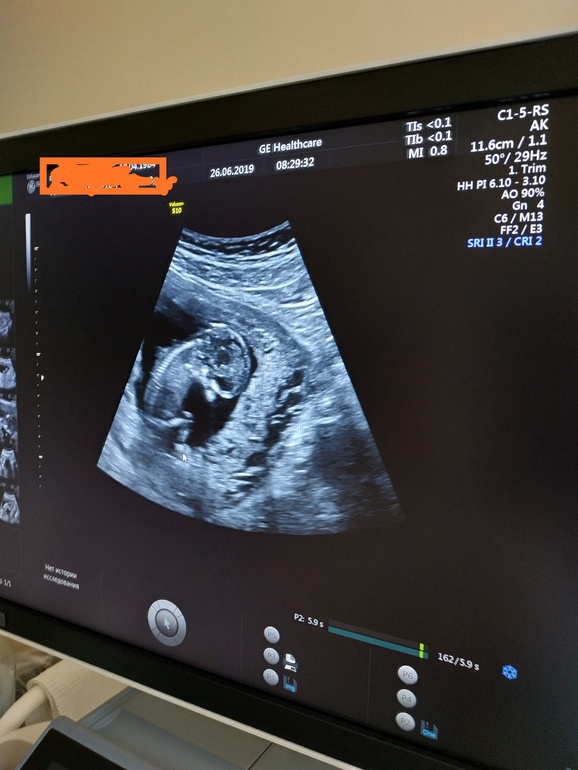

Сегодня 26.06.2019 в ЖК сделали первый скрининг, сказали, что УЗИ без патологий, кровь будет позже. Пол не видно, так как ребёночек спал, сидя, как на стульчике, подперев кулачком носик, узист сказала, что обиделся, что не покормили) больше ничего не сказали. 2 часа провела в жк, от усталости на скамейке во дворике, где потом завтракала забыла копии документов, мне позвонили из жк сообщили об этом, добрые люди принесли туда. Ещё сообщили что результаты УЗИ придут в мою поликлинику, это вообще не поняла, почему... Фоточка моего сонного мыслителя (льницы)